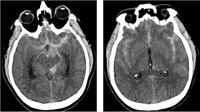

Communicating hydrocephalus in the setting of subarachnoid hemorrhage; note dilation of fourth and temporal horns of lateral ventricles

Courtesy of Dr Salah Keyrouz; used with permission